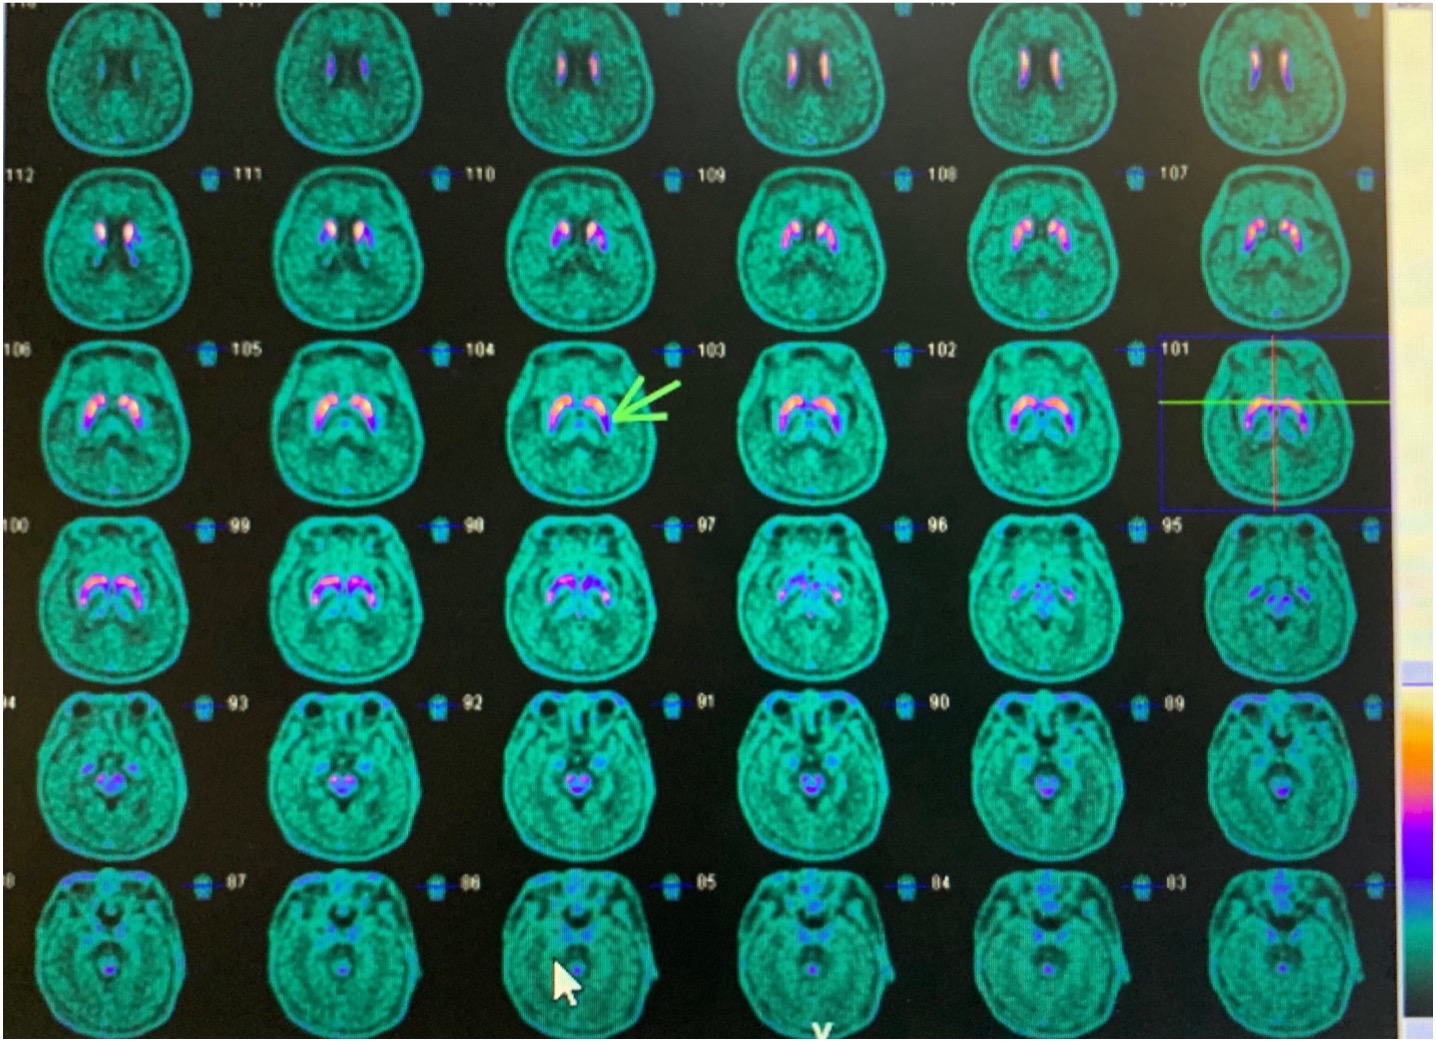

Method: We present a case of a 62-year-old female presenting with subacute onset of bilateral lower extremity tremors at rest and standing, improving with walking. She has anxiety and multiple somatizations but no prodromal PD symptoms. Her tremor exhibited characteristics suggestive of FMD, including intermittent abduction-adduction leg tremors, with amplitude variability, suppressibility, distractibility, and entrainability. Neurophysiological studies showed tremor bursts without variability with synchronous EMG activity between the antagonist pairs, tremor suppression with contralateral hand tapping, and a high coherence between bilateral leg muscles [figure 1A-C]. A score of 3/10 was consistent with functional tremor (FT) based on laboratory-supported criteria (Schwingenschuh et al., 2011; Schwingenschuh et al., 2016). Although bradykinesia and rigidity were absent, reduced arm swing and suppression of leg tremors only with foot tapping, raised suspicion of underlying PD. An F-DOPA PET revealed decreased dopaminergic uptake in the left posterior putamen [figure 2]. A favorable levodopa response confirmed a coexisting neurodegenerative process.

Figure 2.F-DOPA PET:Reduced uptake in left putamen